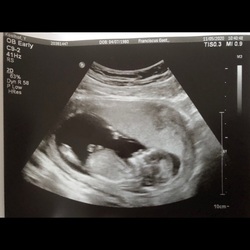

Hier nog 1, sinds een paar dagen. Nu 32 weken precies. Beurs gevoel bij de schede uitstraling naar billen en zo niet prettig met ook omdraaien in bed 🙄..verloskundige gevraagd..ook te horen gekregen ivm indaling. Morgen echo dus dan is er iets meer zekerheid. Zou er ook gewoon om vragen als ik jou was. Sterkte en succes ☺️🙏we can do this!